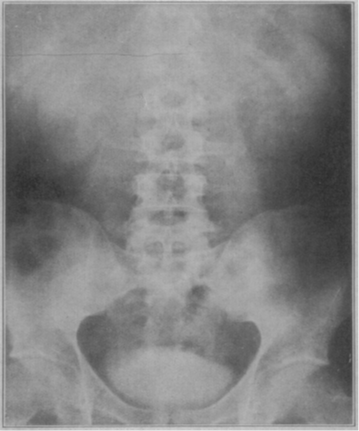

Like the discovery that sodium iodine opacifies the urinary tract, the origins of oral cholecystography are serendipitous, too. As the story goes, Dr. Warren Cole was working in a lab experimenting with compounds that were known to be excreted by the liver into bile. Four and a half months went by before he even ever saw a gallbladder image, until one day this image was obtained in one of the lab dogs.

Now, where is the serendipity in this particular story? The dog’s caretaker forgot to feed that particular dog that morning. (But don’t worry, he got his evening meal!) It was only a few months later that the experiment was successfully duplicated in human subjects. These are images after an administration of the compound showing progressive opacification of the gallbladder by 24 hours, then washout at 32 hours.